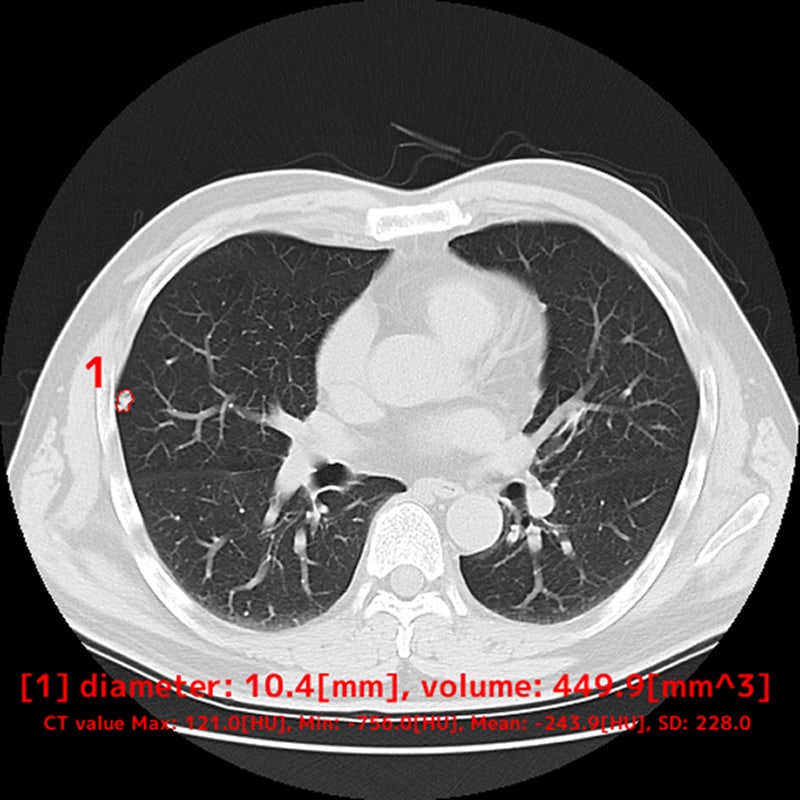

Chest nodule detection support technology that makes an effective diagnosis possible

EIRL Chest Nodule supports the interpretation process by identifying findings suggestive of lung nodules from chest X-rays that are larger than 5 mm and smaller than 30 mm. The sensitivity of the specialized-radiologist and the non-specialized radiologist interpreting the images with the software increased by 9.9% and 13.1 % respectively, suggesting an improvement in diagnostic accuracy.